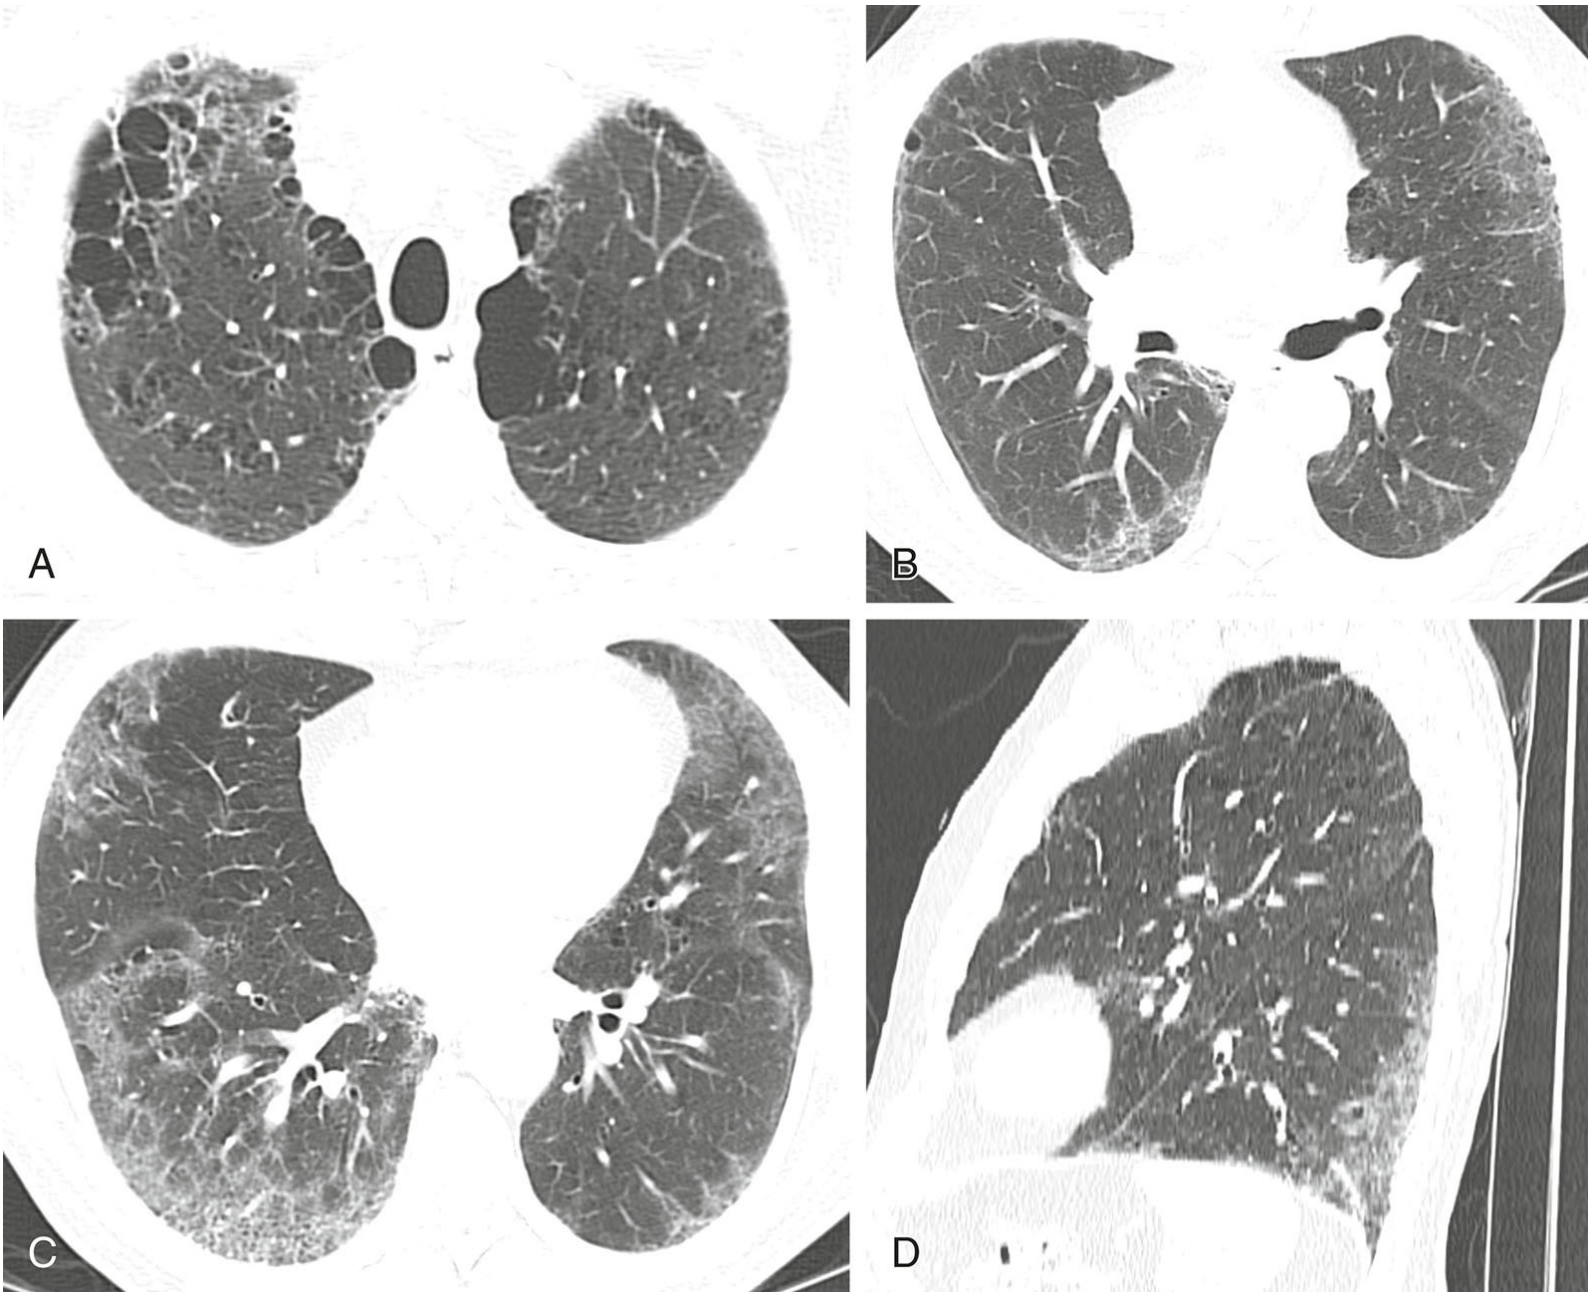

3e46b414d8d39bcbbf86b932d8bc5c4b.png

机化性肺炎的分布。

经上肺(A)、中肺(B)及下肺(C)层面的HRCT图像,显示胸膜下结节和支气管血管周围实变。冠状位重组图像(D)显示病变以肺下叶分布为主。